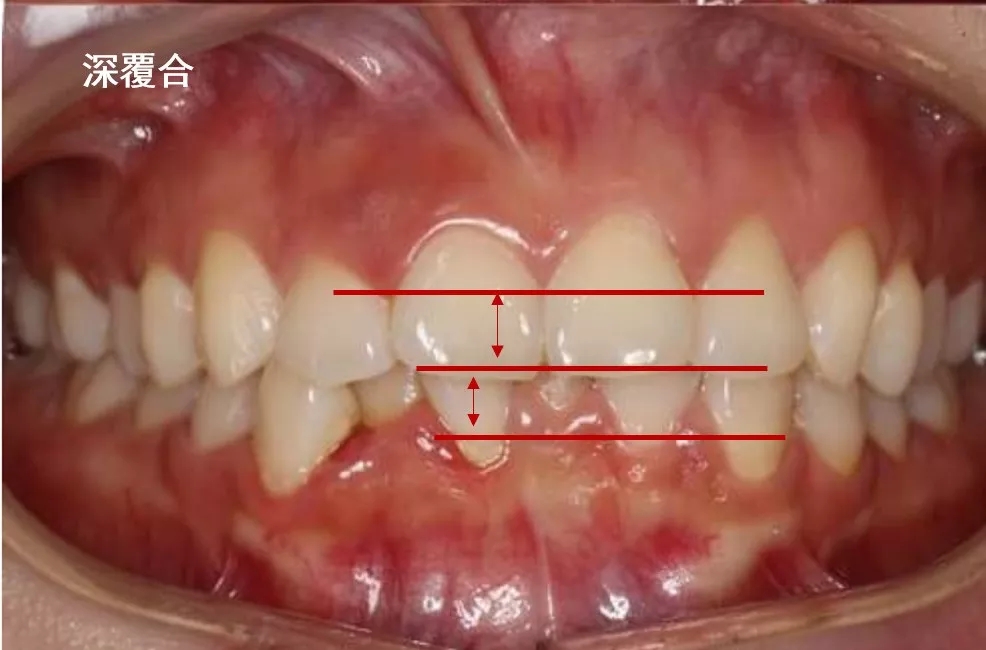

深覆合

深覆合是一种上下颌牙弓和(或)上下颌骨垂直向发育异常所致的错颌畸形。如果上牙包住下牙的范围超过了 2~3 毫米就是深覆合。是指垂直距离过大,是上下关系。

像这样